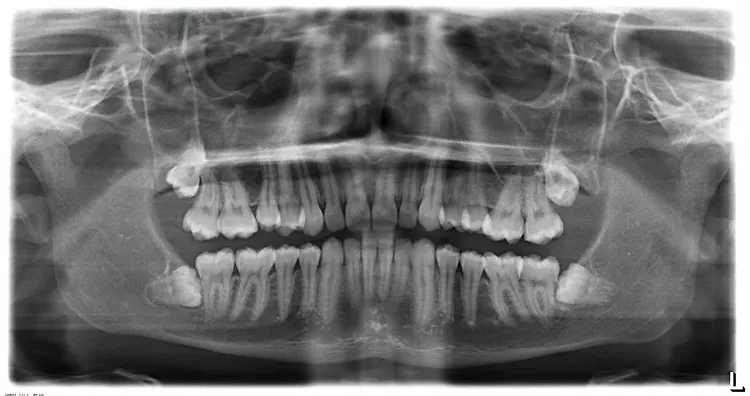

In this case the impacted wisdom teeth are in close proximity of a major nerve. If there are no symptoms present, it may be wise to leave them in position. However, it would be advisable to take an X-ray every 3-4 years to determine that no unwanted changes are taking place.